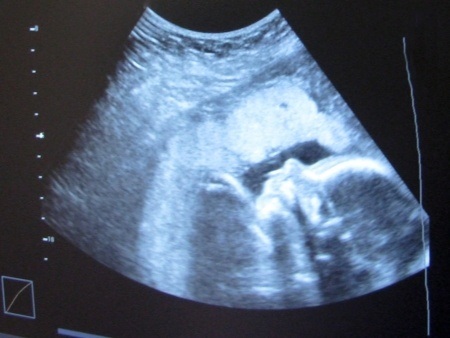

עורך דין רשלנות רפואית, הורים לילד עם שיתוק מוחין תבעו את המדינה. ביהמ"ש: הרופאים לא התרשלו[אילוסטרציה חיצונית: Viktoria Solomkina www.123rf.com]

ההורים טענו כי רופאי "כללית" וצוות בית החולים התרשלו בכך שלא שלחו אותם לבדיקות לנוכח היקף ראש קטן באולטרסאונד. אלא שהשופטת השתכנעה שמדובר בממצא שהתפתח אחרי הלידה.

בנם של התובעים נולד בביה"ח איכילוב בשנת 2006 בניתוח קיסרי. מעקב ההריון בוצע במרפאות "כללית". במהלך השבוע ה-37 להריון, רופא קופ"ח הפנה את התובעת למיון בשל ממצא חריג של היקף הראש. בבית החולים בוצע אולטרסאונד נוסף שהראה שהיקף ראש העובר בטווח הנורמה אולם לנוכח חשד לעצירה בגדילת הבטן ומיעוט במי שפיר, הוחלט ליילד את העובר.

בנוגע לבית החולים, נטען כי לנוכח פער של יותר משתי סטיות תקן בגודל הראש, התובעים טענו כי צריך היה להפנות אותם לבדיקות נוספות כמו סקירת מוח ו-MRI, שהיו מאתרות פתולוגיה מוחית.